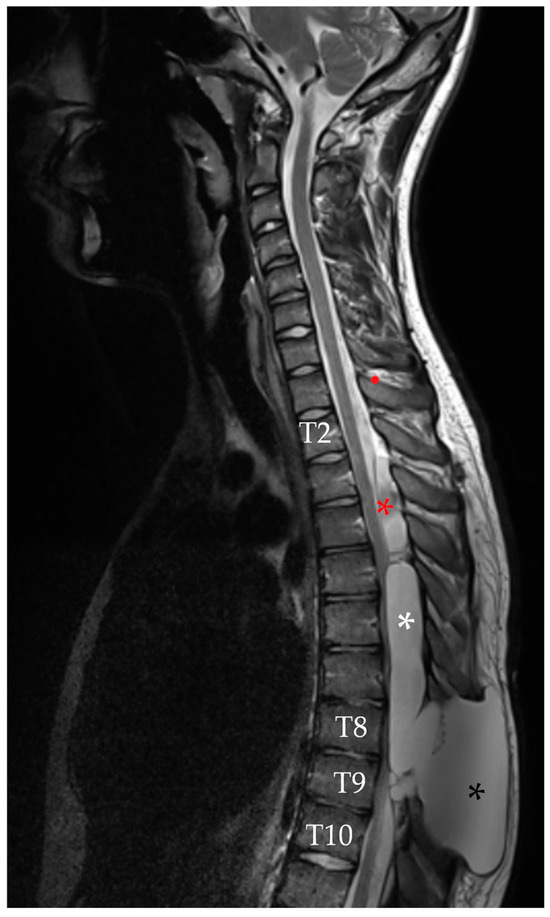

Finally, MRI at 1 week after surgery showed a reduction in size of the pseudomeningocele at the T2–T4 level, along with decreased overall spinal cord compression and almost complete resolution of the caudal pseudomeningocele (Figure 9). The patient remained neurologically stable with mild improvement and no new deficits were observed.

Figure 9. Sagittal T2-weighted MRI performed 7 days after the last surgery, which included percutaneous repair of the dural leak. The result of the blood patch is visible in the upper portion of the spinal arachnoid cavity (white arrow). A marked reduction in the cranial pseudomeningocele (black asterisk) is noted, along with near-complete resolution of the inferior pseudomeningocele (white asterisk).